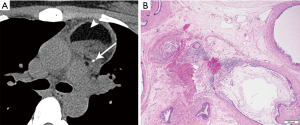

Appearance on CT is often that of a fluid-attenuation cyst. On MRI, a simple cyst will display low T1 and high T2 signal intensity. However, cysts may be complex in terms of fluid attenuation or presence of septations. For this reason, diagnostic accuracy of CT for thymic cysts may be inferior to that of MRI (33,40) (Figure 8), particularly if a cyst is multiloculated or complex. MRI can characterize T1 hyperintense hemorrhagic or proteinaceous inflammation within a cyst, and exclude soft tissue or enhancing septations via post-contrast subtraction sequences.

Of note, thymic cysts may be associated with other prevascular lesions. For example, they may be seen in the setting of thymoma, with an incidence of 15% in a series of 54 resected thymomas (41), as well as thymic enlargement in the setting of lymphoma (42). Chemotherapy, radiotherapy or surgical intervention are other causes of acquired thymic cysts (10).

Comprised of at least two germ cell layers (endoderm, mesoderm, ectoderm), they may show calcium, soft tissue, fat, and fluid (Figure 10). The majority, nearly 90%, have fluid attenuation or multilocular cystic portions. Calcification, which may be coarse, linear, rim or eggshell, has been reported in up to 53%, and bone or teeth in up to 8% (3,8). A tooth would be considered a pathognomonic finding, and a fat-fluid level also a highly specific imaging finding. On MRI, fat saturation technique may reveal to better advantage any foci of macroscopic fat, and the presence of calcium should cause susceptibility artifact. Rupture into the pericardium or pleura can occur, indicated by adjacent pleuropericardial effusions.

Teratomas can be divided histologically into mature (containing mature adult type tissue) and immature (containing embryonal type tissue) subtypes. The histological diagnosis is characterized by the presence of multiple tissue types of epithelial, mesenchymal and neural origin. Skin and subcutaneous tissue are the most common findings, followed by respiratory and intestinal epithelium, fibroadipose tissue, smooth muscle, cartilage, nerve, and brain tissue. Immature teratomas show immature glands characterized by tall columnar cells, fetal lung mesenchymal cells, immature cartilage, and blast-like stroma. Neuroepithelial tissue is the most common.

Extensive examination of a teratomatous tumor is recommended to exclude the presence of non-teratomatous germ cell tumor elements. Whereas teratomas are treated by surgical excision alone, the presence of other germ cell tumor components requires systemic therapy.